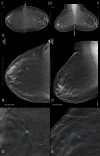

Materials and methods: A deep learning AI system was developed to identify suspicious soft-tissue and calcified lesions in DBT images. A reader study compared the performance of 24 radiologists (13 of whom were breast subspecialists) reading 260 DBT examinations (including 65 cancer cases) both with and without AI. Readings occurred in two sessions separated by at least 4 weeks. Area under the receiver operating characteristic curve (AUC), reading time, sensitivity, specificity, and recall rate were evaluated with statistical methods for multireader, multicase studies.